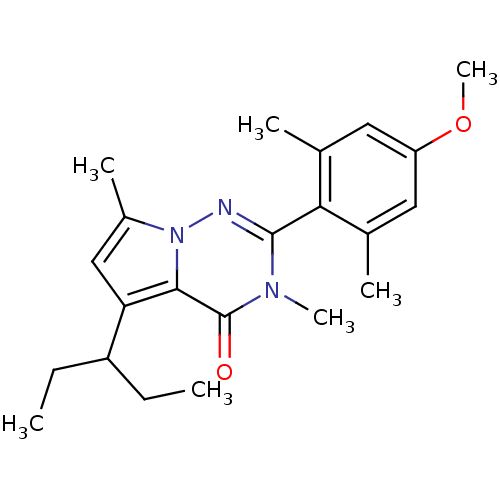

TargetCorticotropin-releasing factor receptor 1(Homo sapiens (Human))

Dupont Pharmaceuticals

Curated by ChEMBL

Dupont Pharmaceuticals

Curated by ChEMBL

Affinity DataEC50: 0.220nMAssay Description:Activity of peptidic agonists on corticotropin releasing factor receptor receptor using agonist-stimulated adenylate cyclase assayMore data for this Ligand-Target Pair